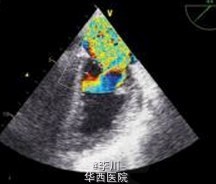

今日我在European Heart Journal(EHJ)上看到一例罕见胸部钝挫伤后乳头肌外伤性破裂致心脏损伤心源性休克:患者,男,27 岁,因“车祸导致多发伤”急诊入院。CT 检查显示 70% 肺挫伤,心电图检查提示窦性心动过速,V3、V4 导联病理性 Q 波,V4-V6 导联 T 波倒置。经食道超声心动图显示二尖瓣严重返流,由前外侧乳头肌断裂所致,心室收缩期乳头肌脱垂至左心房。如下: